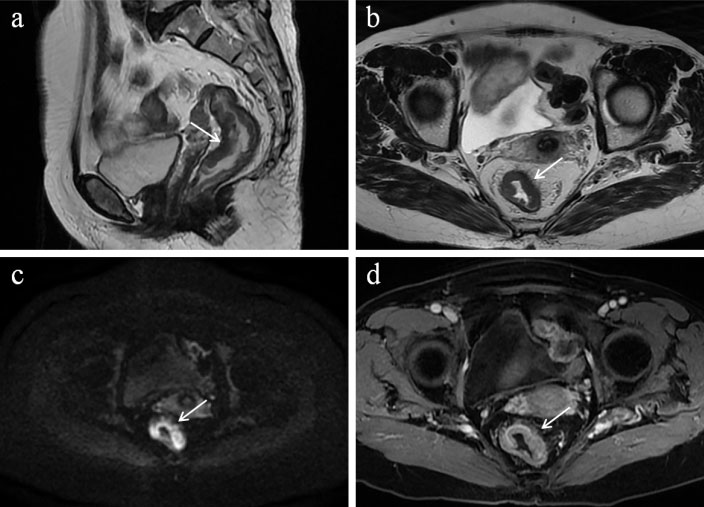

图1:检查结果

女性,40岁,分娩史,便秘5年余,并尿失禁。MRD扫描排便相所示肛管下降35mm、膀胱下降9mm、直肠中度前突16mm(△)。